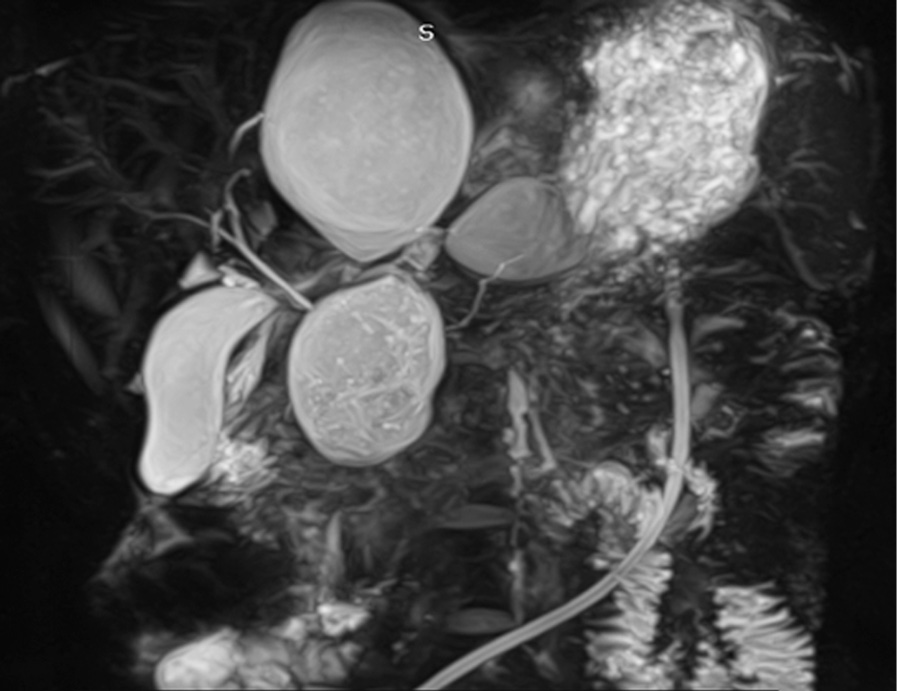

Для уточнения взаимосвязи кист с главным панкреатическим протоком (ГПП) наиболее информативными являлись МРХПГ (Se 100 %, Sp 60 %, Ac 82 %) и эндоскопическая ультрасонография (Se 100 %, Sp 75 %, Ac 89 %) (рис. 1, 2).

Рис. 1. Магнитно-резонансная холангиопанкреатография: множественные посттравматические псевдокисты

Fig. 1. Magnetic resonance cholangiopancreatography: multiple posttraumatic pseudocysts